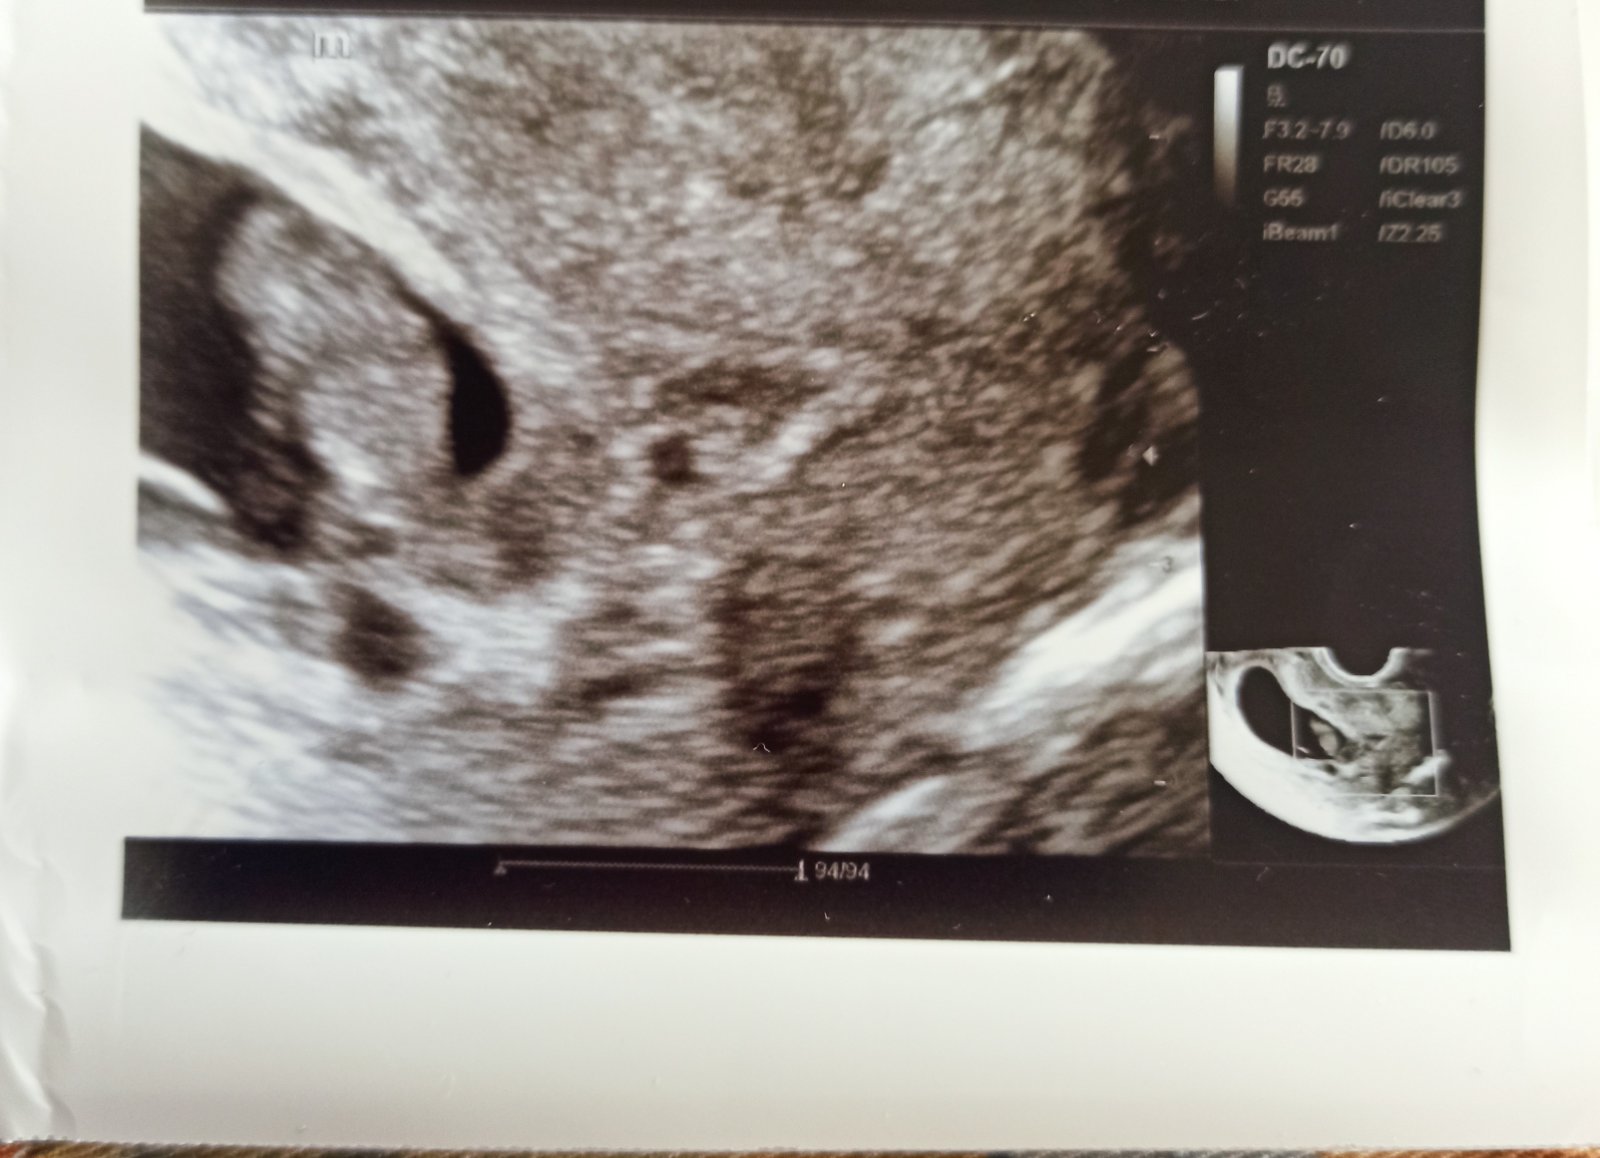

@miskachrumka podľa MS by som mala byť 7tt+4 ale bolo o pár dní väčšie....podľa dr 8+0

Srdiečko bolo uzasne ...bolo to krásne počuť...len beriem progestenale kôli spineniu...no s tým som mala problém aj pri prvom tak dúfam,že to dobre dopadne aj teraz

@babullka1 no super ja idem 21.1 na druhé sono

@miskachrumka ja mám ísť 25.1 dúfam,že bude všetko v poriadku ,mám dosť stresy kôli tomu no dnes má ukludnil to sono....tieto prvé mesiace sú stresujúce....